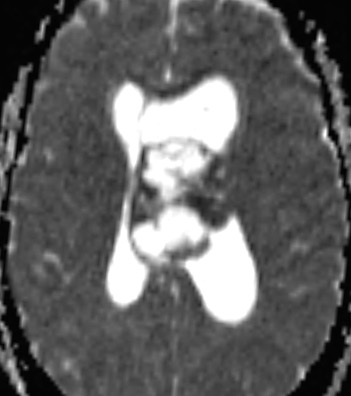

In a central neurocytoma, the areas of enhancement correspond to regions of restricted diffusion and presumed hypercellularity on DWI and ADC (shown here). A coronal T2 MRI can help detect tumor attachment site. Learn more here: zurl.co/9RbK #MedTwitter #Neurosurgery

In a central neurocytoma, the areas of enhancement correspond to regions of restricted diffusion and presumed hypercellularity on DWI and ADC (shown here). A coronal T2 MRI can help detect tumor attachment site. Learn more here: zurl.co/9RbK

#MedTwitter #Neurosurgery